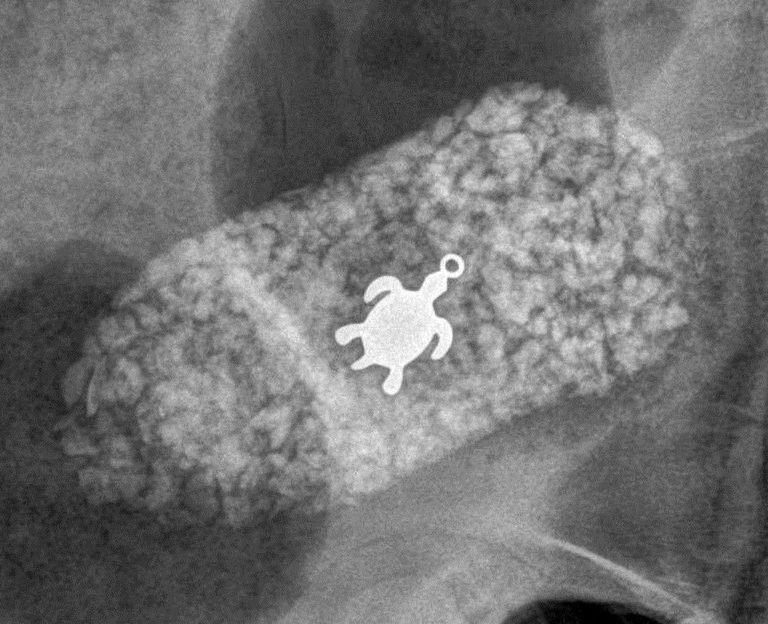

/ 11Świeciło się

Obraz

© Veterinary Practice News / Shannon Edwards, general manager, of Pet Wellness Center in Marion, Ill.

Półroczna udomowiona gęś gatunku pilgrim o imieniu Plymouth trafiła do weterynarza, bo połakomiła się na łańcuszek z krzyżykiem swojej właścicielki. Kobieta pochyliła się na chwilę, a ptak złapał za błyszczący przedmiot i szybko połknął.